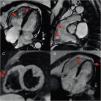

A 45-year-old female patient with no health issues presented to the emergency room for syncope during exertion. The electrocardiogram (ECG) showed negative T waves V1-V3; the laboratory tests and echocardiography were normal. A CMR scan was performed which revealed the following: thin right ventricular (RV) free wall with hypokinesia and multiple microaneurysms, RV end-diastolic volume (RVEDV) of 105 mL/m2 and RV ejection fraction (RVEF) of 32% (Figure 1). Based on the Task Force Criteria for ARVC diagnosis, the patient fulfilled two major criteria and was scheduled for intracardiac defibrillator (ICD) implantation.1 The T wave inversion in the right precordial leads other than V1-V2 should be investigated for underlying structural heart disease that might lead to SCD.2